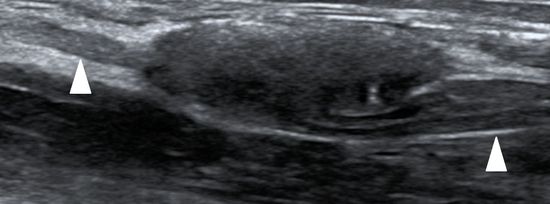

Die klinische Untersuchung der peripheren Nervenverletzung in Kombination mit Nervenultraschall (siehe Beispielbild) und Elektroneurografie sowie Myografie bildet den komplexen Untersuchungsapparat peripherer Nervenverletzungen. Je nach Ursache der peripheren Nervenschädigung erfolgt neben einer Beratung im Rahmen der Sprechstunde eine individuell abgestimmte Weiterversorgung. Eine enge Kooperation mit den Kollegen der hiesigen Neurochirurgie (Prof. Dr. M. Schuhmann et al.) sowie den Kollegen der BG Unfallklinik, Abteilung HPRV (Prof. Dr. A. Daigeler et al.) und unseren Kollegen der Neuroradiologie (Fr. Prof. DR. U. Ernemann) im Rahmen des Tübinger Nerve Teams TNT komplettiert die interdisziplinäre Diagnostik.